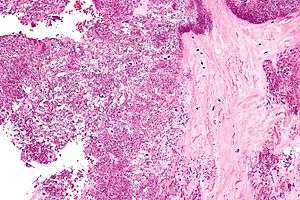

Arthrocentesis, or removing synovial fluid from the affected joint, is performed to test the synovial fluid for the calcium pyrophosphate crystals that are present in CPPD. When stained with H&E stain, calcium pyrophosphate crystals appears deeply blue ("basophilic").[12][13] However, CPP crystals are much better known for their rhomboid shape and weak positive birefringence on polarized light microscopy, and this method remains the most reliable method of identifying the crystals under the microscope.[14] However, even this method suffers from poor sensitivity, specificity, and inter-operator agreement.[14]